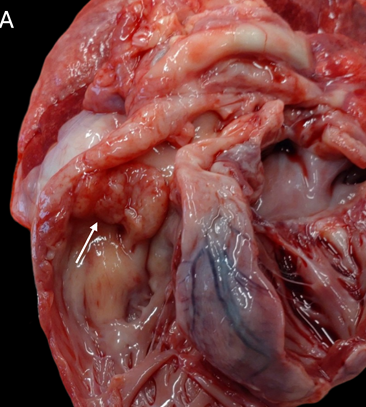

- 부검 소견: 부검을 통해 폐동맥 판막과 관련된 종괴가 우심실로 확장되어 우심실 및 우심방 심근을 침윤하고 있음을 확인하였고, 이로 인해 심한 유출로 및 판막성 폐동맥 협착증이 발생했음이 밝혀졌습니다. 또한, 흉수, 경미한 심낭 삼출액 및 복수도 확인되었습니다. 좌측 신장이 현저하게 불규칙하고 커져 있었으며, 췌장과 횡격막에서도 결절성 병변이 관찰되었습니다.